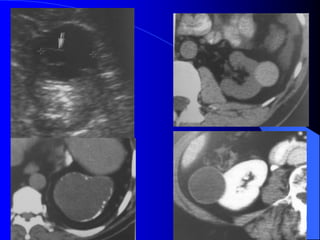

- Siãu ámphán biãût âæåüc khäúi âàûc vaì dëch. Nãúu laì khäúi âàûc seî xem xeït cáúu truïc ám, coï thãø giaím, âäöng hoàûc tàng ám, xem âäü âäöng nháút ám, väi hoïa. Nãúu laì khäúi dëch, seî tçm täø chæïc âàûc hoàûc vaïch trong nang. Siãu ám coï thãø tháúy haûch di càn, xám láún ténh maûch. Noïi chung khi phaït hiãûn khäúi âàûc trãn siãu ám, cáön chuûp CLVT âãø âaïnh giaï roî hån baín cháút, sæû xám láún, di càn.

- CLVT phánbiãût khäúi âàûc hay dëch, phaït hiãûn väi hoïa nhoí, xuáút huyãút trong u, tçnh traûng tæåïi maïu cuía u. Pháön låïn træåìng håüp phán biãût âæåüc u laình vaì u aïc. Xem xeït âæåìng dáùn niãûu bë giaîn, bë xám láún. CLVT kiãøm tra di càn haûch xám láún vuìng xung quanh, xám láún maûch maïu, di càn xa, cå såí âãø phán giai âoaûn tiãún triãøn u, cáön thiãút cho phæång phaïp âiãöu trë.

- Càõt låïpvi tênh Hçnh aính u giaím tè troüng so våïi nhu mä tháûn vaì tàng tè troüng sau khi tiãm TCQ. CLVT coï thãø tháúy: Maïu cuûc vaì soíi trong âæåìng dáùn niãûu coï tè troüng cao hån u (20-30UH). Soíi 100 - >1000UH tuìy thaình pháön cáúu taûo vaì maïu cuûc 50-70UH. U bãø tháûn coï thãø thám nháûp nhu mä laìm thay âäøi båì tháûn, coï thãø laìm heûp tàõc âæåìng baìi xuáút, giaîn ÂBT, coï thãø phaït hiãûn âæåüc trãn NÂTM. CLVT phaït hiãûn u bãø tháûn xám nháûp nhu mä tháûn dãù hån, âäöng thåìi phán biãût âæåüc våïi u nhu mä tháûn xám láún bãø tháûn.